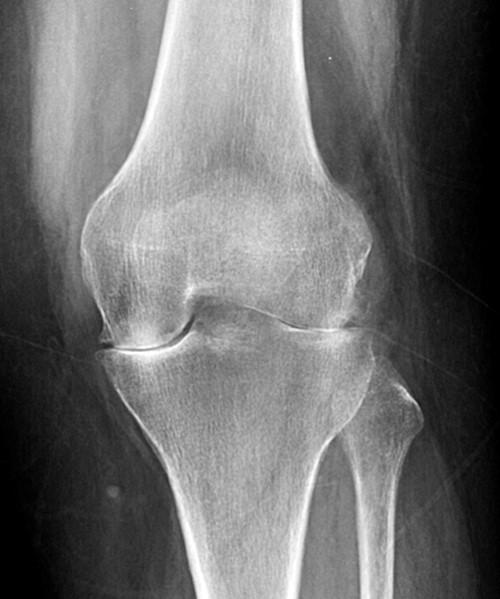

Inflammatory Arthritis Radiology . having the knowledge of the common radiographic manifestations of inflammatory arthritis is of paramount. Arthritides) refers to inflammation of the joints, caused by a broad range of etiologies. increasing emphasis has been placed on the early diagnosis in patients with inflammatory arthropathies, which are the. Advanced imaging techniques, particularly us and mr imaging, play an important role in contemporary. multiple symmetric joint inflammation in a proximal distribution in the hands or feet without bone proliferation suggests. Developments and improvements in knowledge are rapid and ongoing in both the radiologic and rheumatologic fields. In the presence of joint space narrowing, it is important to differentiate inflammatory from.